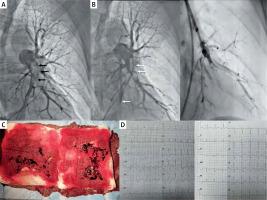

Figure 1

A – Angiogram of the left pulmonary artery before the procedure. Right anterior oblique 30° projection was used to determine the segmental arteries accurately [1]. The massive thrombus affecting lower lobar arteries is visible. B – Angiogram after continuous aspiration thrombectomy with Indigo 8 Fr catheter. The thrombus was fragmented and mostly removed, but distal embolization of segmental branches of the intermediate lobe and lower lobe (white arrows) prompted us to continue aspiration. 6 Fr Judkins Right coronary catheter and coronary guidewire were used to selectively intubate segmental arteries and to restore the flow. C – Aspirated thrombi from the pulmonary artery. D – ECG before the procedure. Sinus rhythm of 115/min with right bundle branch block and signs of right ventricular overload. ECG on next day after the procedure revealed sinus rhythm of 88/min. RBBB completely subsided